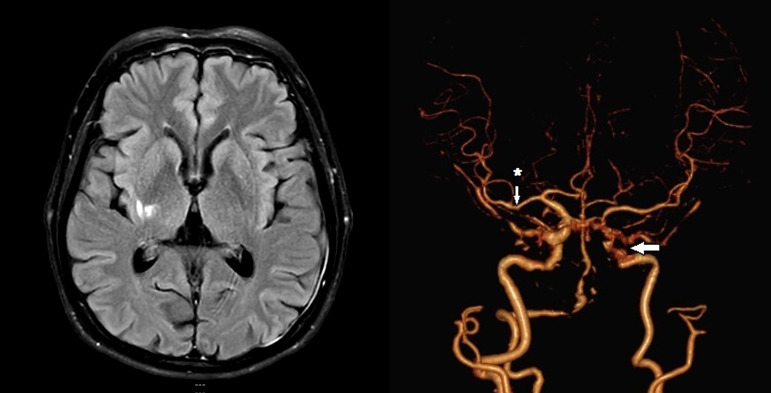

Results: Among 234 acute NCIS cases, 113 exhibited ICAS, 12 had ECAS, 20 had both, and 89 had neither. The RNF213 rs112735431 gene variant was detected in 2 patients, both heterozygous A/G. The frequency of the RNF213 rs112735431 variant was 0.9% (2/234; 95% CI: 0-2.1%) in acute NCIS patients and 1.8% (2/113; 95% CI: 0-4.2%) in ICAS. All individuals with the RNF213 variant were males with hypertension, diabetes mellitus, dyslipidemia, and ICAS, without a family history of ischemic stroke.

Abstract Image